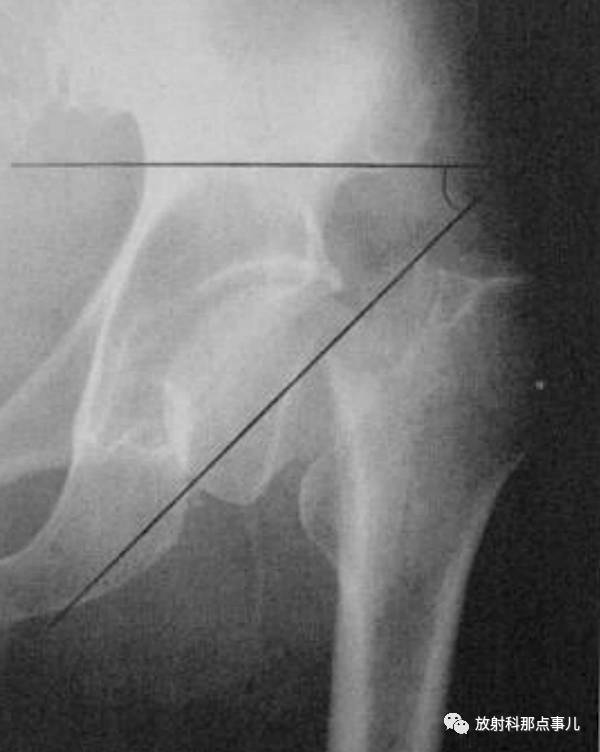

Power角

在骨盆正位片上,通过两侧髂前上棘作一水平线,然后再划股骨颈骨折线的延长线,两线相交所成的夹角。此角小于30° 者,为外展型骨折,骨折易愈合;大于30° ~90° 者,为内收型骨折,需手术纠正。